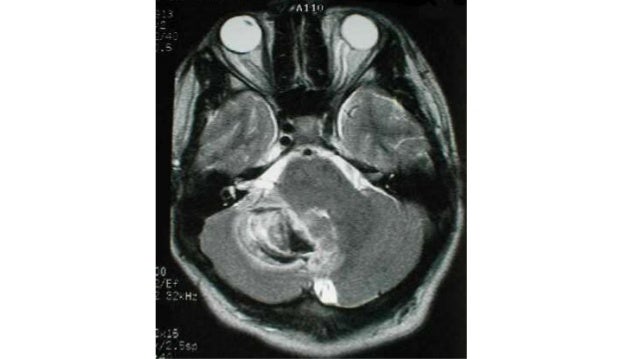

16 mar 2021 3. kanker rahim (endometrium) kanker endometrium atau rahim adalah pertumbuhan cepat sel-sel pada endometrium (lapisan rahim). Vertigo terdapat 2 macam yaitu vertigo sentral & vertigo perifer, yg membedakan keduanya adalah penekanan atau letak gangguan organ yang menjadi penyebab vertigo itu sendiri. karena central vertigo adalah origin of letak gangguannya tidak selaras maka secara gejala dan tanda-indikasi yang timbul bisa dibedakan antar keduanya. Vertigo of central origin this type of vertigo is caused by pathology in the brain. in general, they are not accompanied by cochlear symptoms. the origin may be ischemic in the cerebellum, brain stem, or tumor in the posterior fossa.